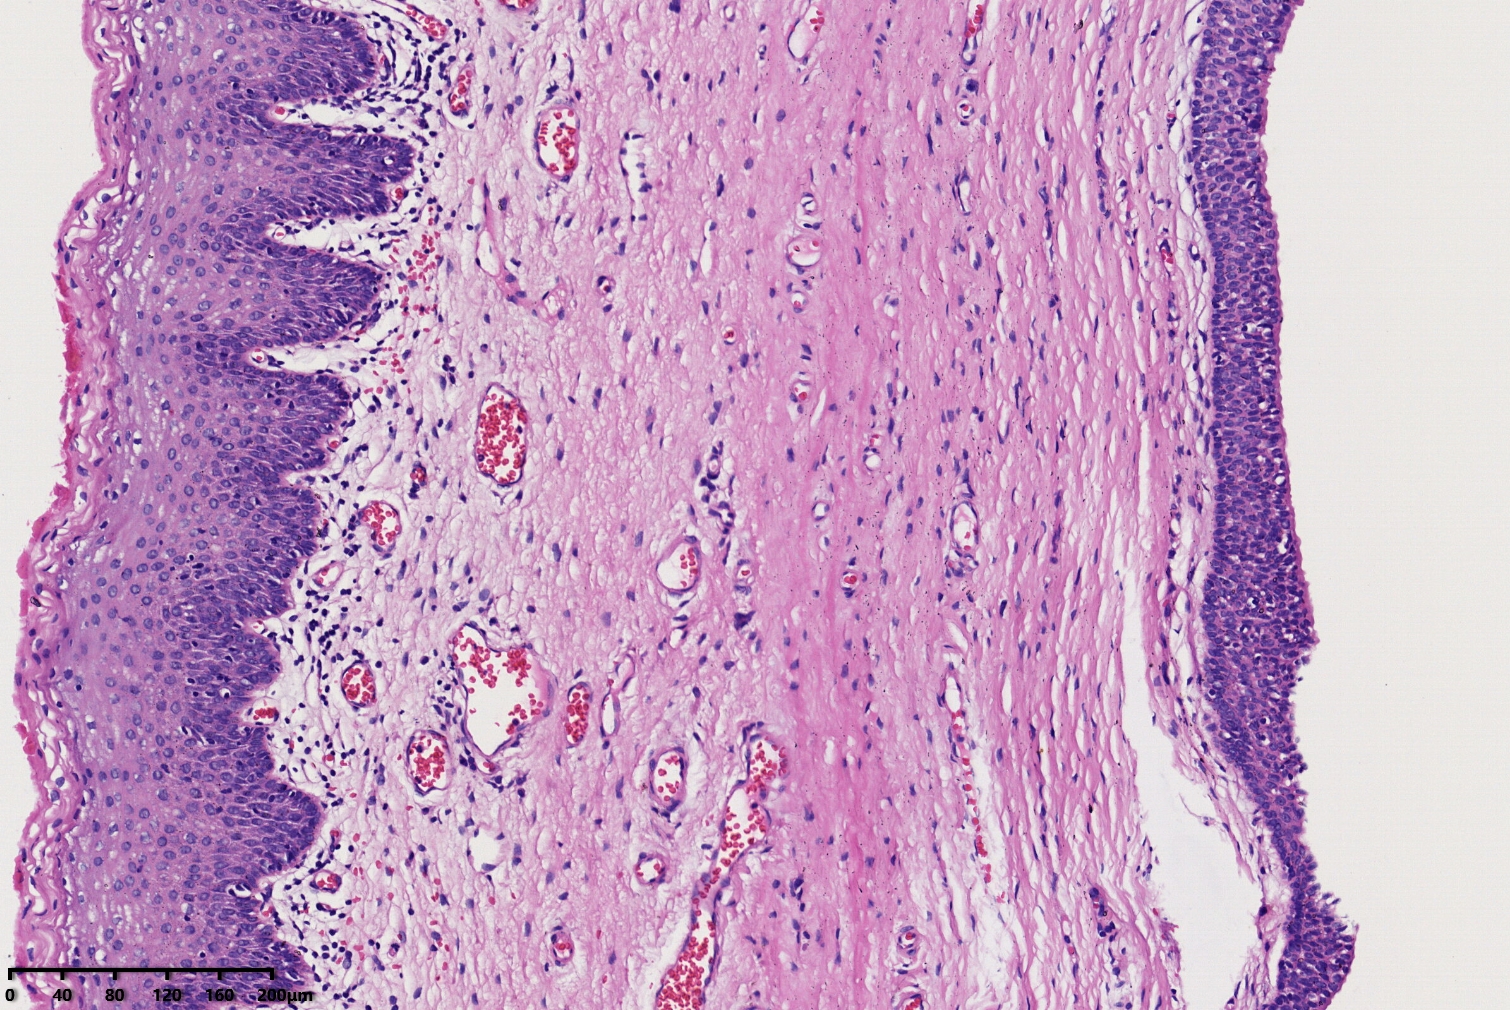

阴道口囊肿,前庭大腺囊肿?

阴道口囊肿2年

阴道口囊肿

汗腺囊瘤?

包涵囊肿,内衬鳞状上皮

还是考虑前庭大腺囊肿